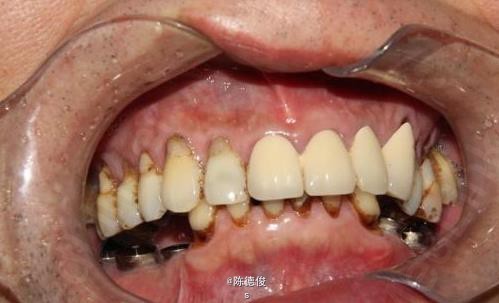

男,64岁,下颌多颗牙缺失数年,身体健康,无烟酒嗜好。

诊断:肯氏1类缺失 诊疗方案:种植固定桥修复+咬合重建 种植系统:瑞士ITI-Straumann种植系统 治疗周期:3个月